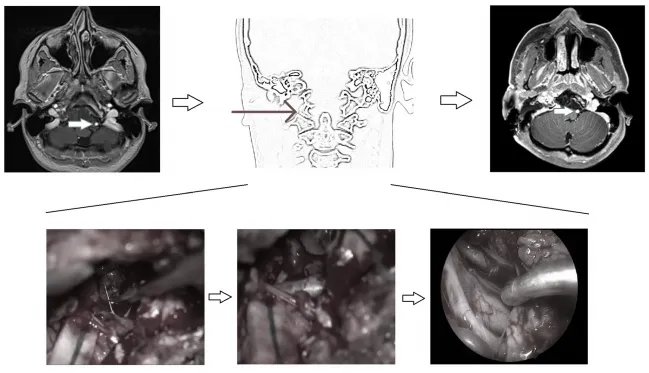

使用前外侧入路的开颅手术的说明性案例。左侧图像:术前MRI显示颅颈交界区脊索瘤包裹左侧椎动脉硬膜内部分(箭头)。中间图:从右侧显示手术入路的示意图,以及从左侧椎动脉逐步剥离肿瘤的术中图像,在手术结束时内镜下可以看到两个保存完整的椎动脉。右图:术后MRI显示肿瘤完全切除,左侧椎动脉通畅(箭头)。